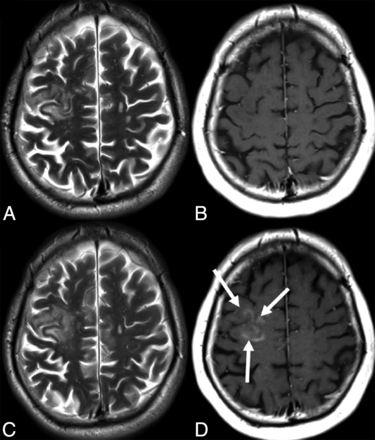

DIR sequences simultaneously suppress CSF and white matter signals, thereby increasing the detectability of gray and white matter lesions in MS significantly.99 Several reports have shown the utility of DIR and PSIR images for detecting MS plaques, especially in intracortical or mixed white matter–gray matter areas compared with FLAIR and T2-weighted images (Fig 4).88,100,101 Hagiwara et al102 recently showed that such sequences could be recreated by using synthetic MR imaging techniques, which lead to greater diagnostic accuracy than conventional MR images in comparable acquisition times.

DIR (A), PSIR (B), and FLAIR (C) images from a single patient with MS at the same section location. An intracortical lesion is evident in the left parietal area. Also, note the excellent overall delineation of the gray-white matter border on PSIR. Reprinted from Nelson et al.100

Last, there have been studies that have combined the above imaging advances with promising results. Calabrese et al103 showed that the combination of DIR and DTI constitutes a substantial step forward in the analysis of cortical disease in MS. They combined these techniques to analyze the cortex of patients with relapsing-remitting MS and found that fractional anisotropy was significantly increased in cortical lesions compared with normal-appearing gray matter. Their study concluded that there is a high correlation between the fractional anisotropy of normal-appearing gray matter and the progression of physical disability during a 3-year follow-up. Another example is the combined use of DIR and PSIR, which allows more reliable detection of cortical lesions in MS than DIR techniques alone. The addition of PSIR also provides better delineation of lesion boundaries, which results in a more confident classification of lesions as purely intracortical, mixed, or juxtacortical.100